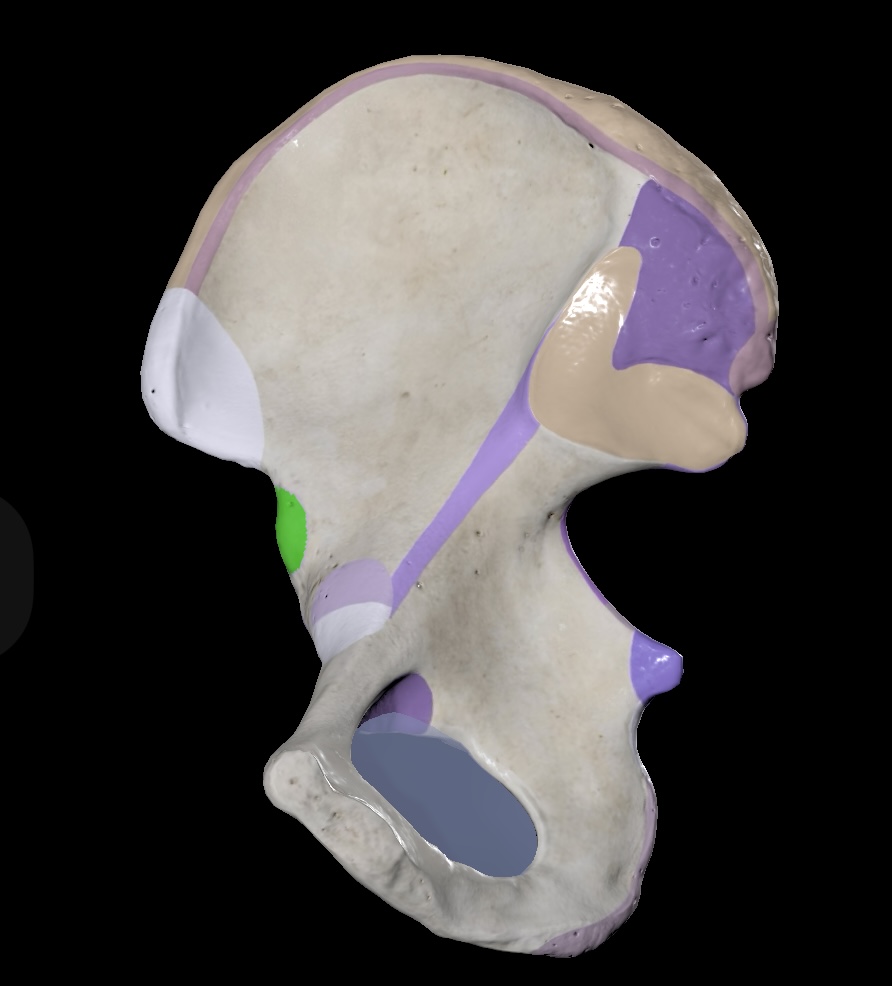

Illium

Ischium

Pubis

Ischial Spine of Ischium

Iliac Tuberosity of Illium

Anterior Superior Iliac Spine

Anterior Inferior Iliac Spine

Posterior Superior Iliac Spine

Posterior Inferior Iliac Spine

Iliac Crest

Acetabulum